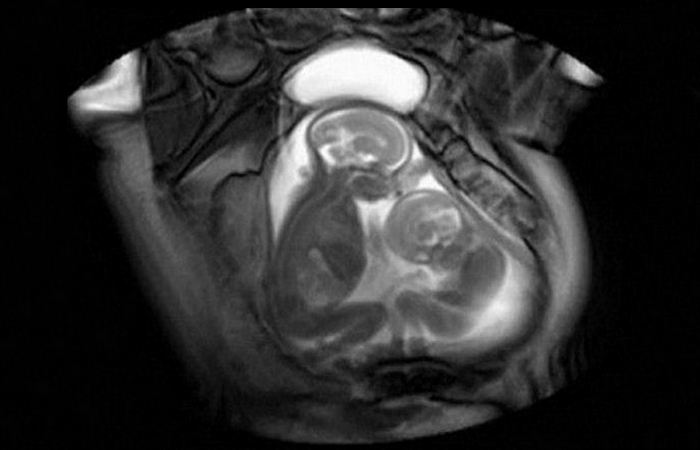

Счастье и радость, умноженные на два.

Близнецы — очень увлекательное и необычное явление. Хотя генетика и медицинские исследования не стоят на месте, все еще есть много вещей, которых люди не знают о близнецах.